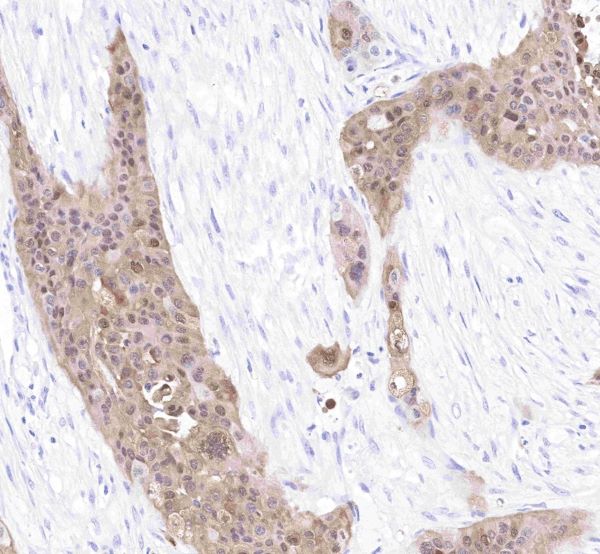

- Ultra-High Specificity & Clear Staining Localization: Precisely recognizes the S100P protein, exhibiting strong cytoplasmic staining specificity in formalin-fixed paraffin-embedded (FFPE) samples. With a clean background and accurate antigen localization, it provides a reliable basis for pathological interpretation—avoiding false positives from cross-reactivity.

- In laryngeal cancer research, S100 antibody IHC staining revealed that S100-positive DCs are primarily distributed in the tumor stroma and among suprabasal keratinocytes.

- This distribution suggests DCs may uptake and present tumor antigens through direct contact with tumor cells, activating specific immune responses. S100 antibodies thus provide an essential tool for exploring immune cell-tumor cell interactions in the tumor microenvironment.